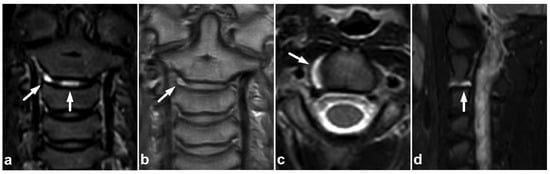

Figure 21.

(a) NECT, coronal reconstruction with a bone kernel. (b) NECT, sagittal reconstruction with a bone kernel. (c) Sagittal STIR. (d) Coronal STIR. A 9-year-old male, neck pain and midline cervical tenderness after diving into shallow water. Small osseous fragments were seen at the anteroinferior corners of vertebral bodies C5 and C6 (arrows). The imaging appearance was consistent with inferior ring apophyses, but due to cervical spine symptoms and high-risk injury mechanism, MRI was performed. STIR imaging did not show any edema, neither in the proximity of the ring apophyses nor elsewhere in the spine. The apophyses were not visible at MRI.